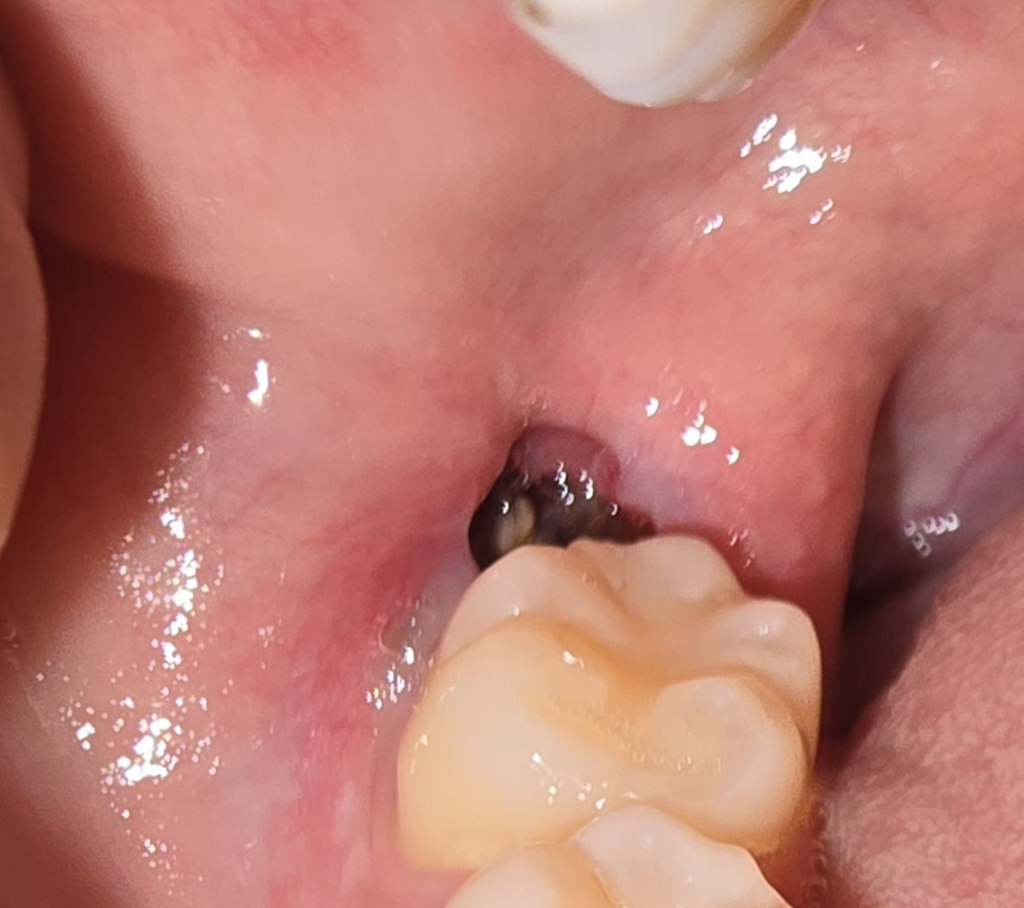

발치한 부위를 자극하게 되면 혈병이 제거되어 치유가 늦어질 수 있습니다. 내부에 이물질이 들어갔다고 해도 내부에 있는 이물질을 억지로 빼내려고 하지 않는 것이 좋습니다. 부드럽게 가글을 해서 제거를 해주는 것이 좋으며 빠지지 않는 것 같은 느낌이 든다면 치과에서 진료를 받아보는 것이 좋습니다. 발질 한 부위는 보통 2주 정도가 지나면 아물기 때문에 그 이전에는 해당 부위를 자극하지 않는 것이 좋습니다

아직 잇몸이 온전히 아물지 않은 상태입니다 초기 치유 후 완전히 잇몸이 아물고 완전히 잇몸뼈가 자라려면 2~3달은 있어야 합니다 그동안 음식물이 껴있지 않도록 칫솔질 및 가글을 부드럽게 잘해주시기 바랍니다